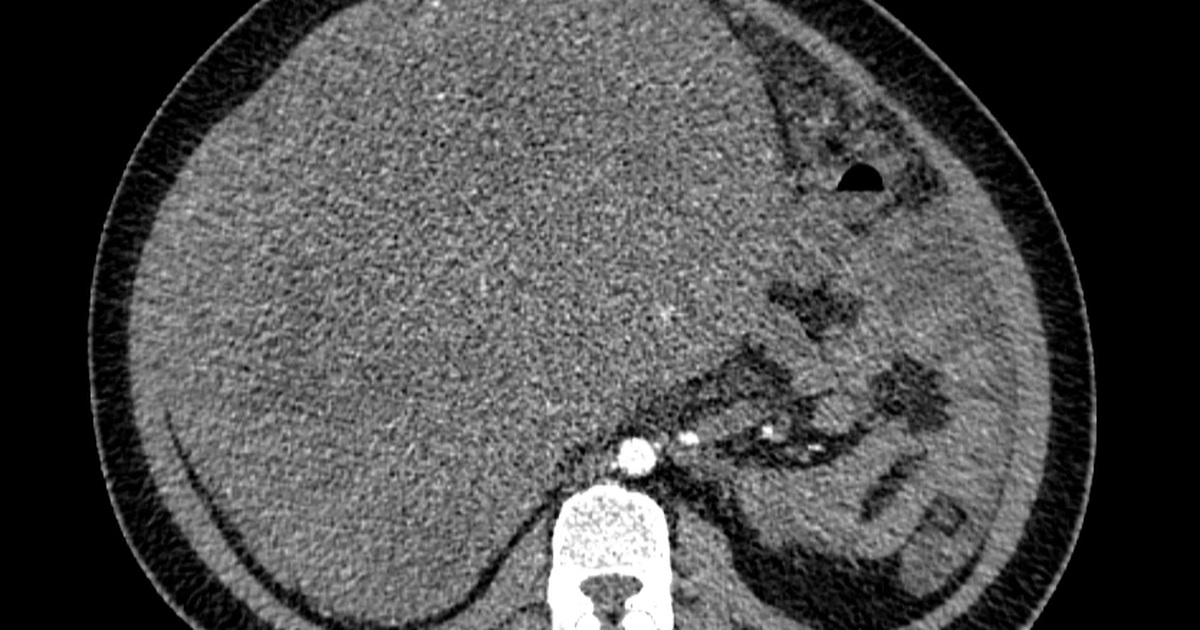

Người bệnh sau đó được lên kế hoạch cầm máu để xử lý những tổn thương xuất huyết do giãn mạch. Tuy nhiên, tình trạng của bà N.H. khá phức tạp khi diễn tiến trên nền bệnh lý đa cơ quan sẵn có - bao gồm xơ gan và đái tháo đường type 2 - đòi hỏi phải điều trị phối hợp thận trọng và chính xác.